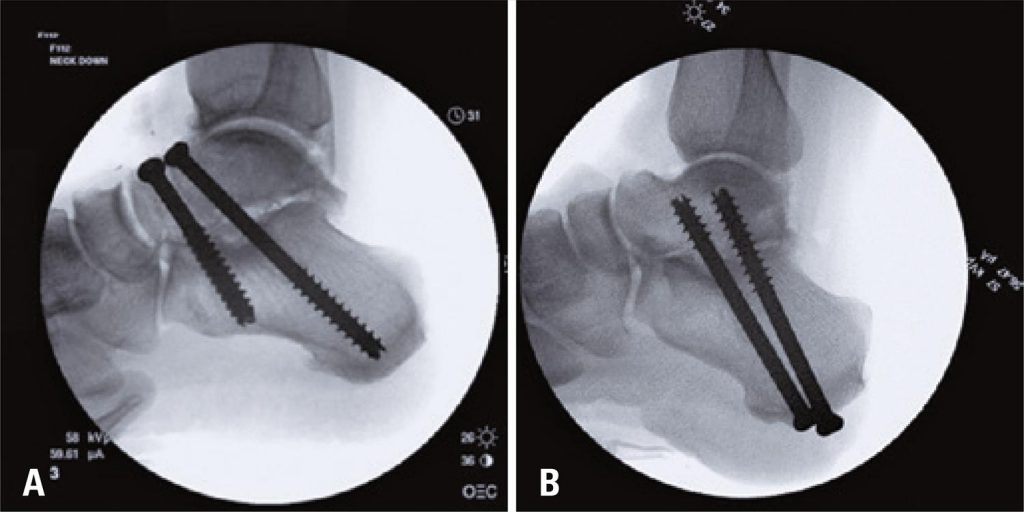

Oito pares de pés de cadáveres frescos foram submetidos à artrodese da articulação subtalar com dois parafusos canulados de 7,3mm. A randomização foi usada para atribuir a orientação do parafuso, de modo que um pé em cada par foi designado com orientação de dorsal para plantar (Grupo DP), e o outro pé com orientação de plantar para dorsal (Grupo PD). Técnica cirúrgica padrão com radioscopia foi usada para os procedimentos. Após a fixação, cada amostra foi testada até a falha com um dispositivo Bionix®858 MTS, aplicando força axial descendente a uma distância para criar torque. O torque de falha foi comparado entre os Grupos DP e PD, usando o teste t de Student, com p=0,05 usado para determinar significância estatística.